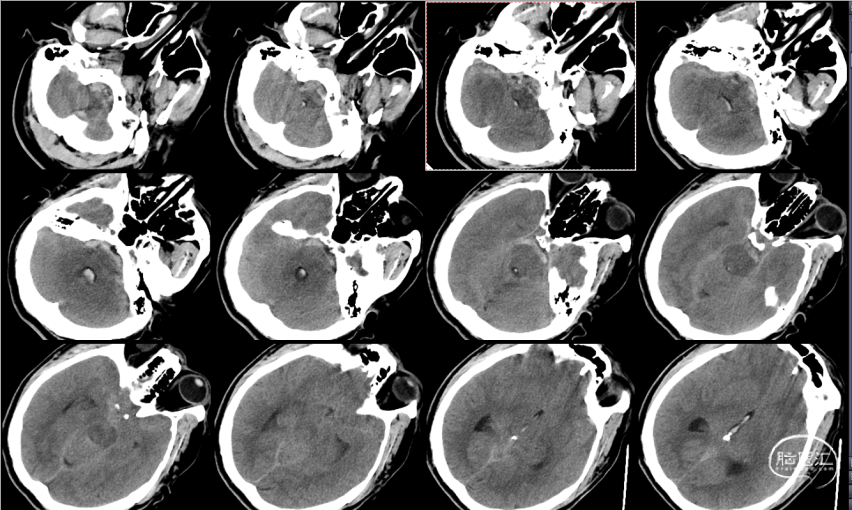

头颅CT:

蛛网膜下腔出血,以脑干前方密度较高,

并逆流入四脑室。

术后检查:次日CT

术后4天,肺部CT显示吸入性肺炎明显好转

术后14天,头颅CT示蛛网膜下腔出血完全吸收,头痛缓解,痊愈出院。